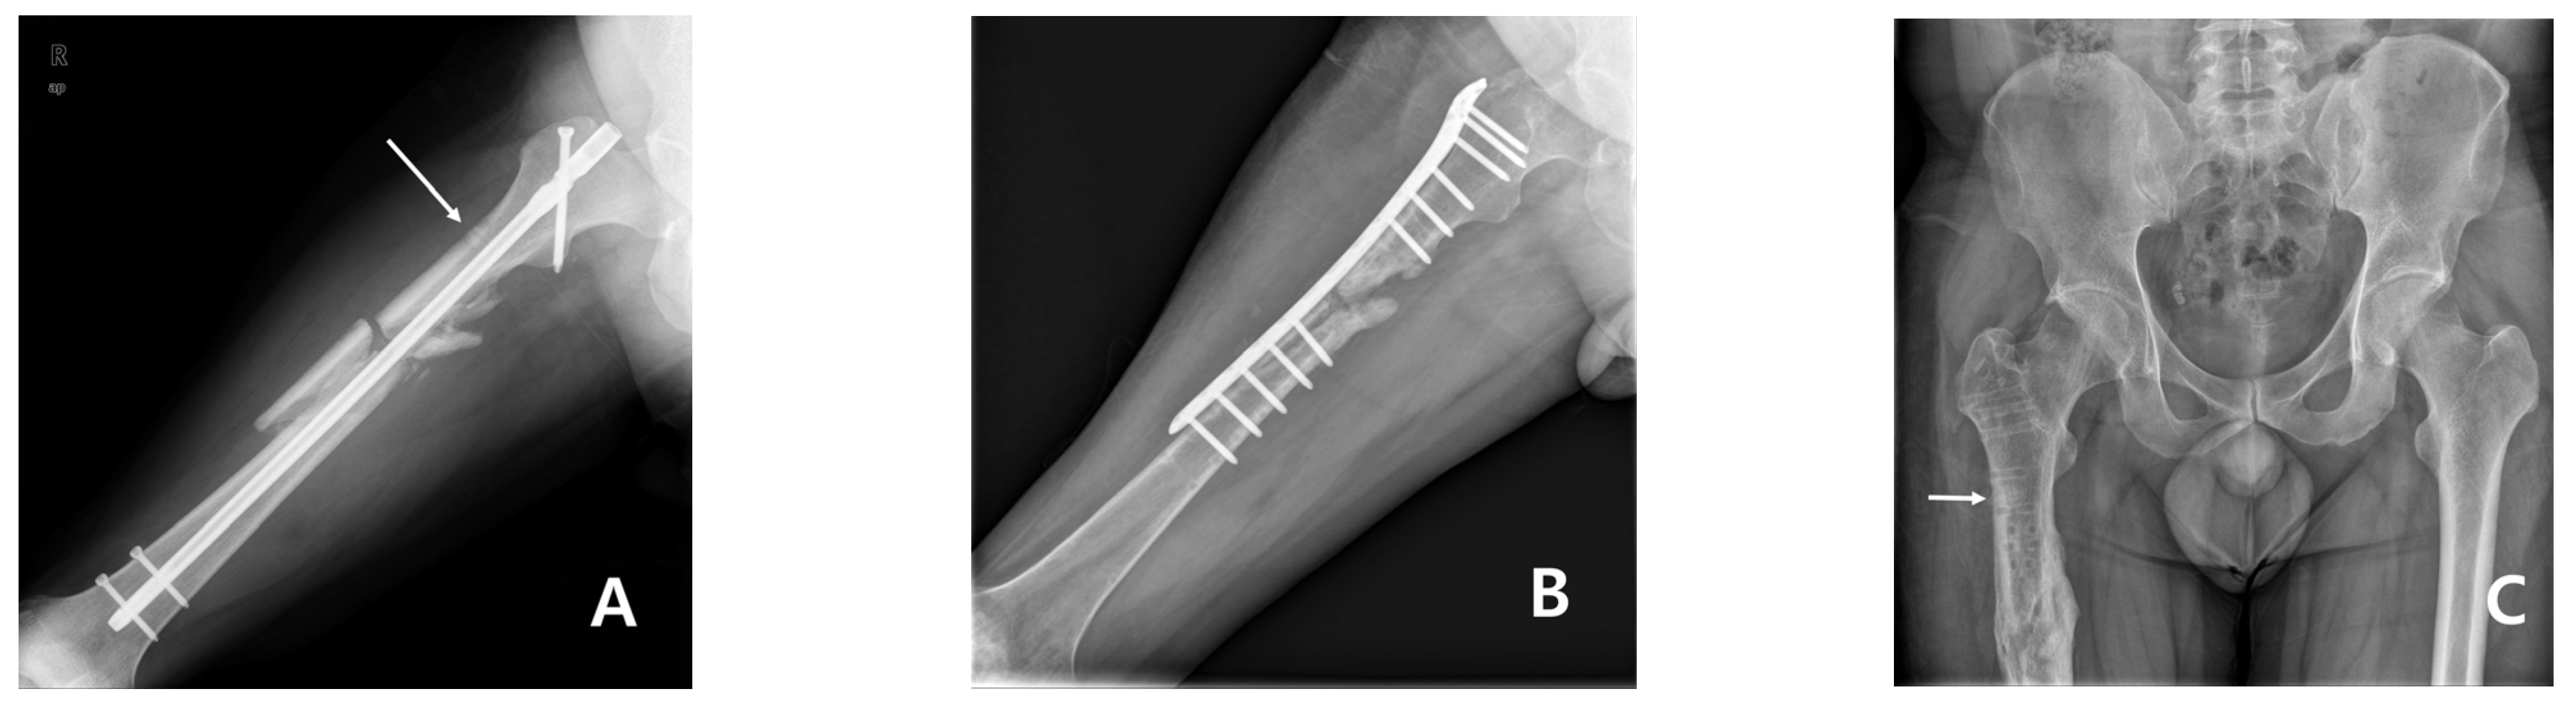

From www.mdpi.com

Medicina Free FullText Subtrochanteric Insufficiency Fracture Steinmann Pin Fixation Surgeon judgement is required to ensure a pin is appropriate for the indication. Pin insertion insert 2 pins on each side of the fracture in the safe zones. Transarticular steinmann pin fixation was first described in 1947 by rowe and sutherland [10]. Steinmann pin is indicated for use in the fixation of bone fractures, bone reconstruction, and as guide pins. Steinmann Pin Fixation.

Postoperative xray image. Multiple Steinmann pin fixation is seen. In Steinmann Pin Fixation The size of the pin chosen should be adapted to the specific indication. Proximal pins should be inserted from anterior to posterior. A rod is fixed to each end of the pin. Pin insertion insert 2 pins on each side of the fracture in the safe zones. Steinmann pin is indicated for use in the fixation of bone fractures, bone. Steinmann Pin Fixation.